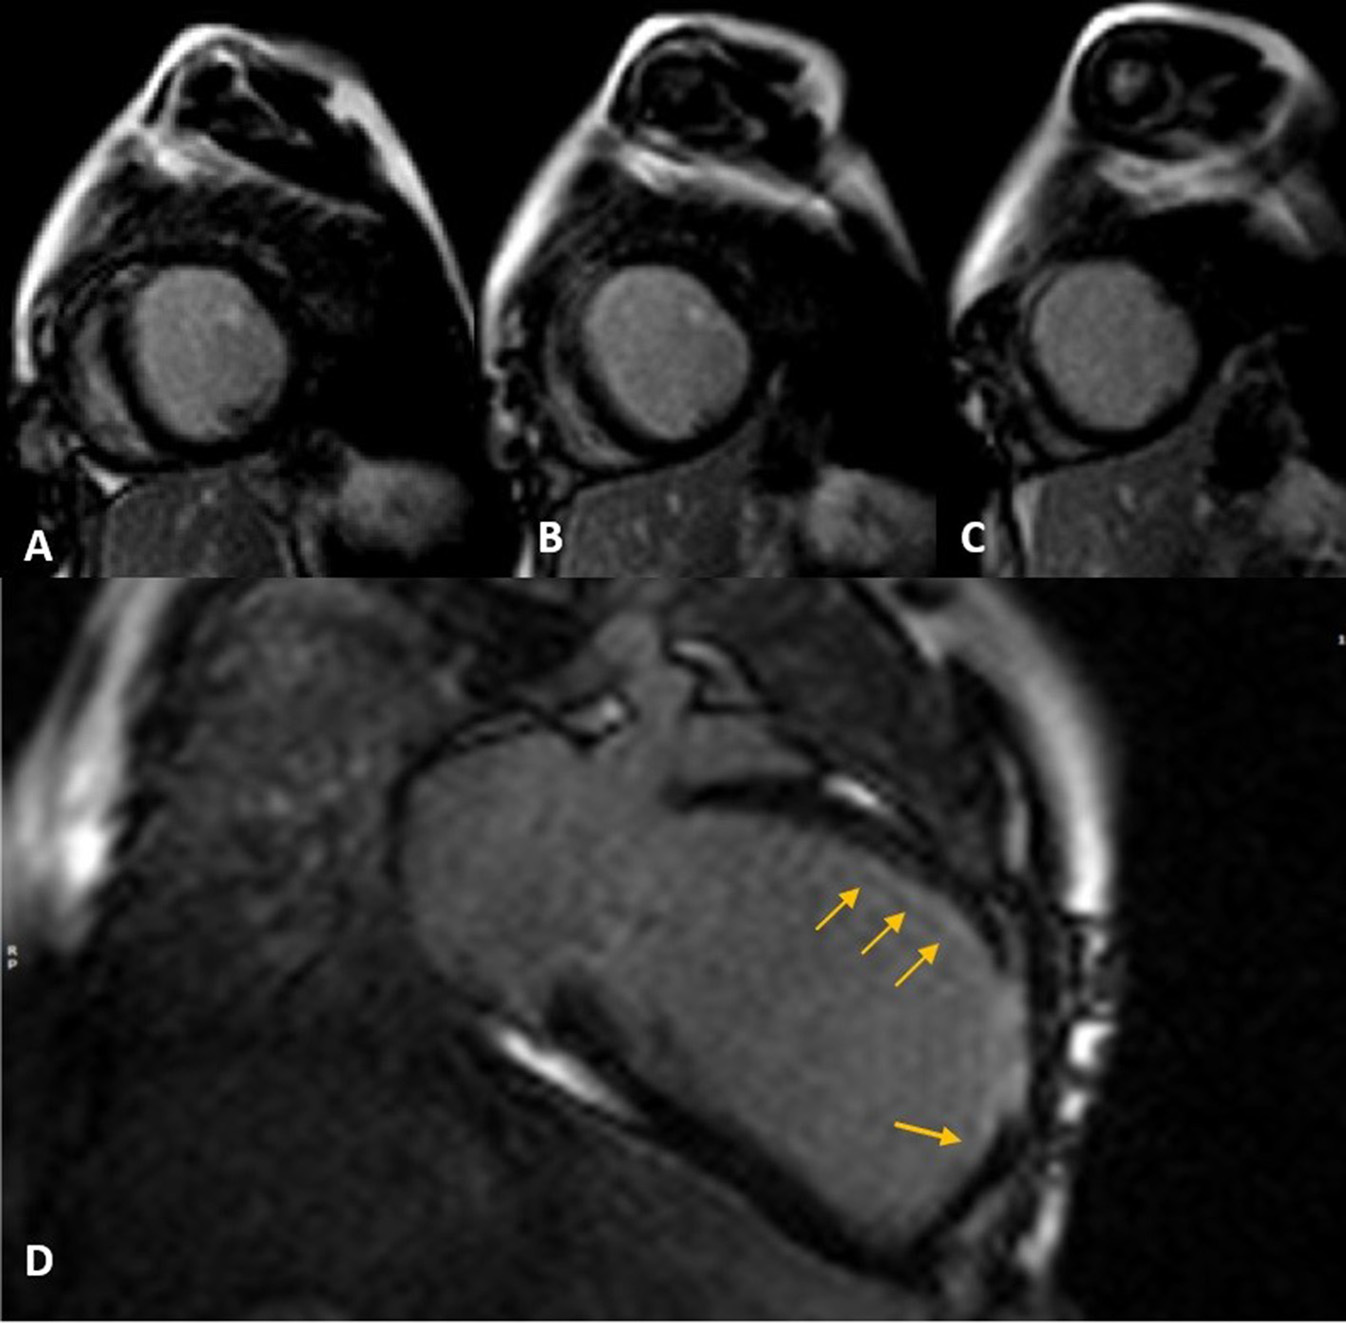

Cardiac magnetic resonance was performed to investigate the possible underlying pathology, which confirmed severe LV dilation, severely reduced systolic function (LVEF: 22%), and severe MR (Figure 2). Late gadolinium enhancement (LGE) sequence demonstrated subendocardial to transmural scar in the basal and especially at the mid anterior and anteroseptal segments, raising suspicion of an ischemic insult. Gated CT coronary angiography (Figure 3) demonstrated an absent LM stem with a centripetal filling of the small caliber confluent LAD and circumflex, likely from collaterals from a dilated right coronary artery. Angiography confirmed the LM atresia with a retrograde collateral filling of LAD and LCX arteries from a dominant RCA. There was no connection to the pulmonary arterial branches (Figure 4; Supplementary Videos 1, 2). Considering the extent of myocardial fibrosis, small-sized coronary arteries and LV remodeling were required, and according to the decision of heart team specialists, the patient underwent medical treatment for heart failure and was scheduled for a heart transplant.

Figure 2

Late gadolinium enhancement (LGE) sequence images in short (A–C) and long (D) axis views show subendocardial (thin arrows) to transmural scar concentrated in mid-anteroseptal and anterior LV segments.